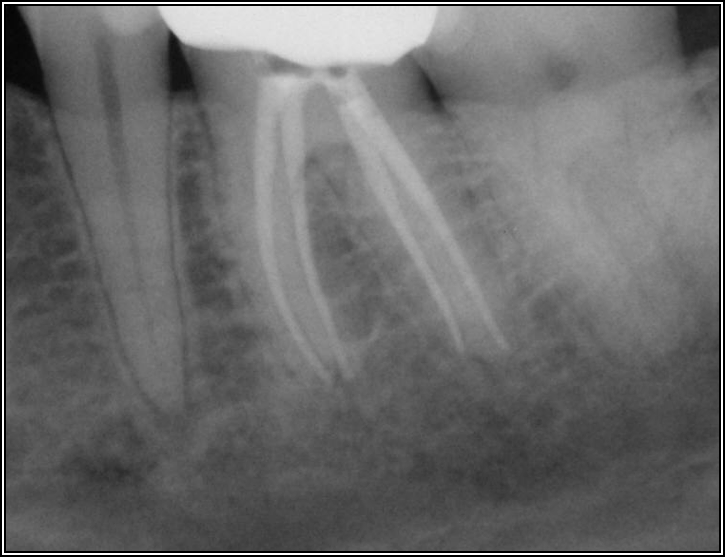

Ultimately, the aim in endodontics is to preserve the tooth as long as possible for the patient. A clinician may want to do a root canal but must face realistic concerns, such as not having enough tooth.Figure 1 shows a case where the clinician was able to access four canals through a zirconium crown, with limited access. Generally, it is preferable to err on the side of opening larger and cleaning out well. If the access is too small, three problems arise: (1) clinicians may not clean effectively; (2) there is a greater chance of separation because there is not enough of a straight path, and (3) canals may be missed. Conversely, if clinicians open too large, they can destroy the tooth. There is a happy medium where the result is fine-tuned and engineered perfectly. Although the perfect result is not always possible or ideal, clinicians continue to strive for it. The best approach is to find the canals and then open them up under a microscope to get enough access. This gives the clinician whatever shape is needed for conservative access.

Fig 1. Limited access.

Figure 1